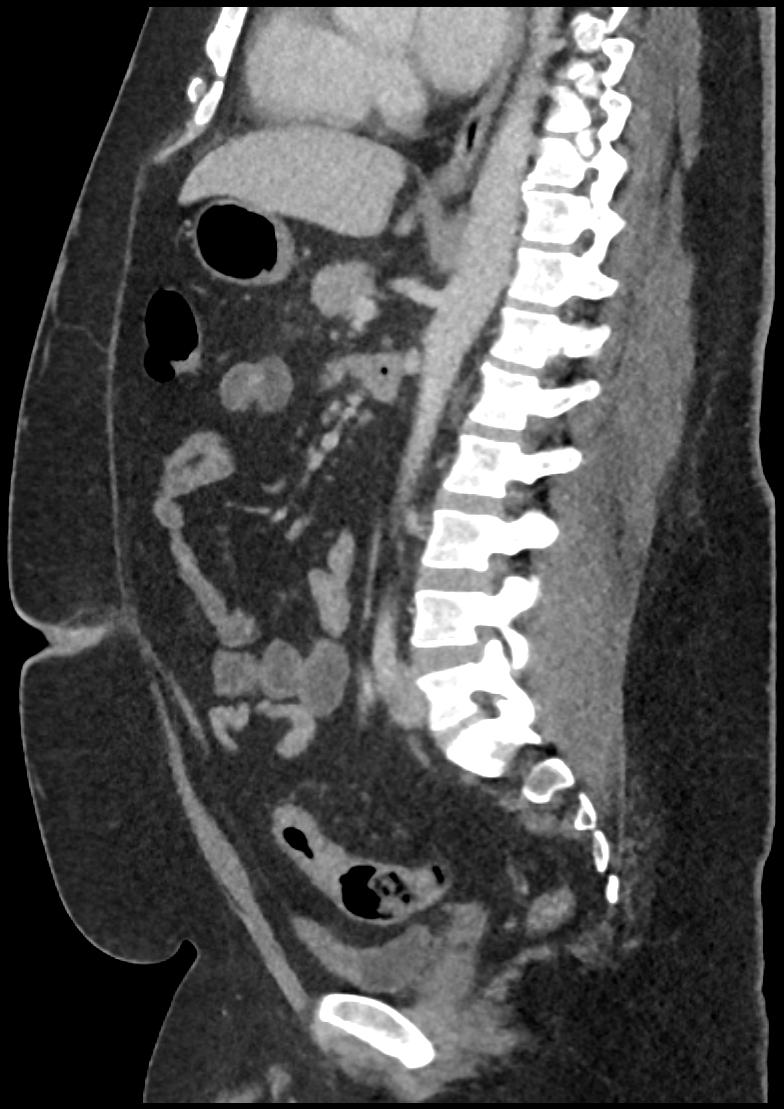

Patient: Padmakumar A. , *1988-04-24, PID: 3000069741773230809

Study Description: CT ABDOMEN

Image Series: Abdomen Sag 3mm [4]

<< Previous | Image 84 of 158 | Next >>